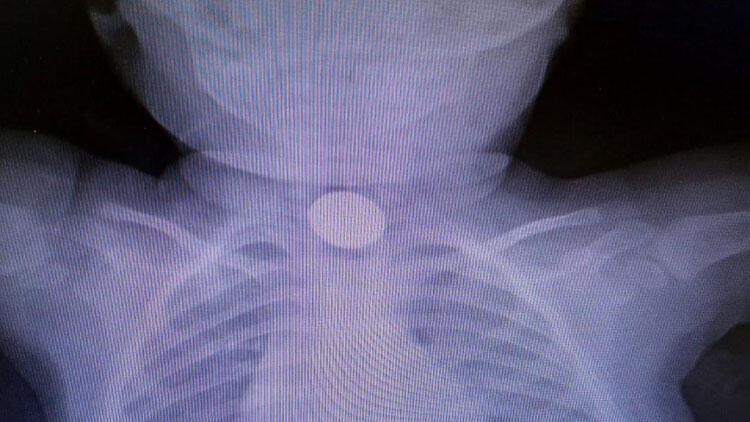

Ereğli’de evde oynarken madeni para yutan 1 yaşındaki D.D.Ç., ailesi tarafından özel hastaneye kaldırıldı. Doktorların müdahalede bulunduğu D.D.Ç.’nin çekilen röntgeninde 25 kuruşluk madeni para sindirim sistemi girişinde tespit edildi. Yapılan muayenede madeni paranın bebeğin yemek borusuna zarar vermediği anlaşıldı. Doktorların müdahalesi sırasında D.D.Ç., kusması sonucu madeni para kendiliğinden çıktı. Sağlık durumu iyi olan D.D.Ç., taburcu edildi.